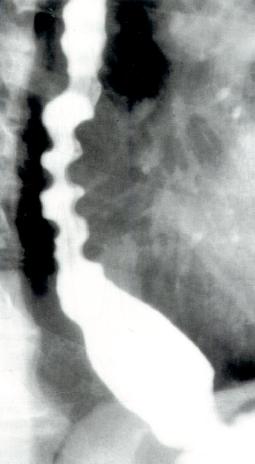

食管X线检查

X线吞钡可用于观察食管并显示食管是否扩张。贲门失弛缓症的特征性X线表现为胸部食管扩张伴液平。LES逐渐变细使食管呈现鸟嘴样外观(图2.7)。

图2.7 贲门失弛缓症的食管X线表现。